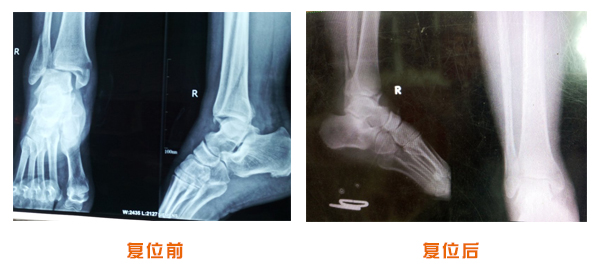

肥城市安駕莊梁氏骨科醫(yī)院是一所以梁氏手法正骨配合膏藥為特色的現代化??漆t(yī)院。

梁氏骨科術始創(chuàng)于清雍正年間,歷經八代,至今已有三百年歷史。據1929年泰安縣志載“梁瑞圖先生,字增生,號蓮峰,安駕莊人,精岐黃并發(fā)明接骨,凡跌打車凡跌打車軋皮不破而碎骨者......【詳細】 |